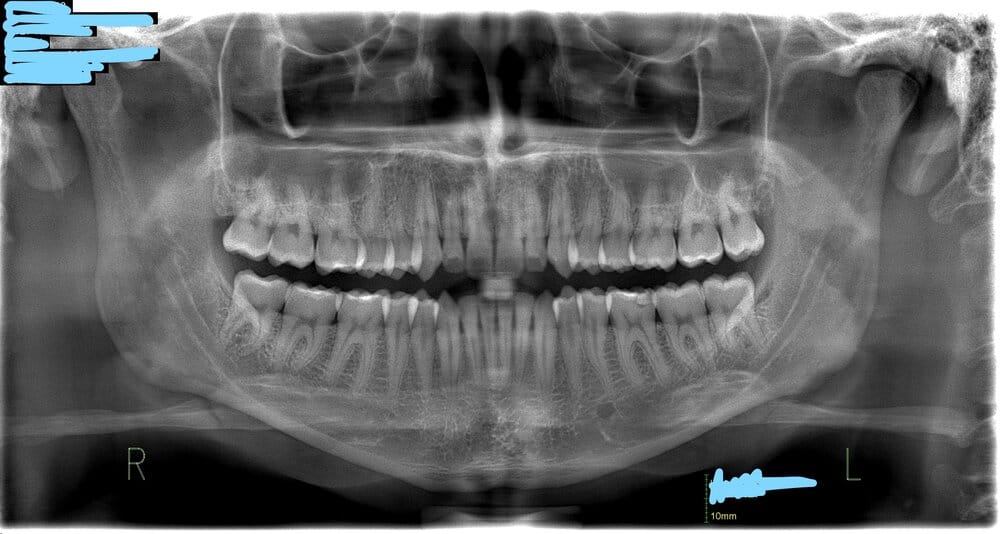

And here's the front view if its of any help:

B